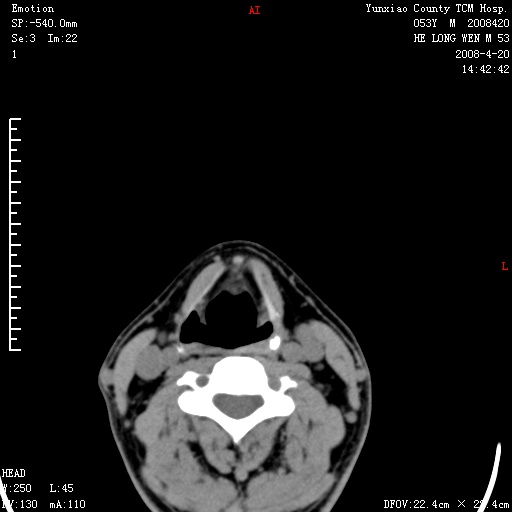

双侧扁桃体肿大:考虑化脓性扁桃体炎。

双侧扁桃体肿大 ,考虑扁桃体炎。

双侧扁桃体肿大,建议结合临床!

双侧扁桃体肿大 ,考虑扁桃体炎

能强化就强化,不能强化就喉镜检查。如怀疑扁桃体肿大,应再往上扫

应该有症状,体检此部位不是常规体检项目,支持双侧扁桃体肿大 ,考虑扁桃体炎,但还是强化一下吧。

双侧扁桃体肿大,考虑扁桃体炎,应做一下增强

显示部分为舌扁桃体,腭扁桃体未见显示。会厌显示欠规则,建议喉镜。

病史太简单,体检?扁桃体是有增大,不会就这么简单吧?